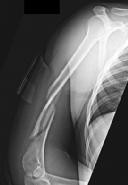

Figures 1 and 2 are the radiographs of a 19-year-old man with a closed right humeral shaft fracture as well as a right femoral shaft fracture and a left ankle fracture-dislocation after a motor vehicle collision. On initial examination, he is noted to have a complete radial nerve palsy of his right upper extremity.

Postoperative radiographs are shown in Figures 3 and